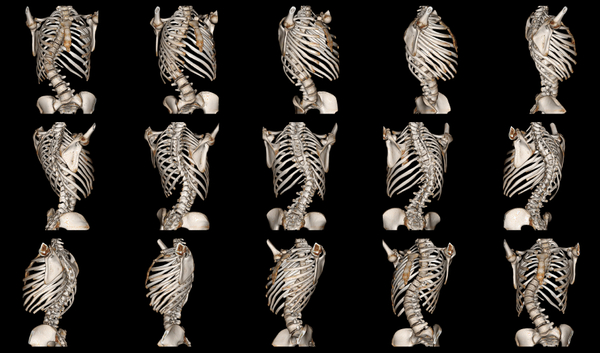

Сколиоз – это многоплоскостная деформация. Суть в чем, в норме наш позвоночник имеет изгибы в сагиттальной плоскости: шейный и поясничный лордоз, грудной кифоз.

При сколиозе эти изгибы уменьшаются (изменение в сагиттальной плоскости), появляются сколиотические дуга/дуги (изменение фронтальной плоскости).

Из-за торсии происходит скручивание грудной клетки (ребра прикрепляются к позвонкам), появляется реберный горб.

При больших деформациях могут еще и нервы “защемляться”. Но не грыжами, а просто между позвонками, когда межпозвоночные отверстия экстремально сужены. При сильном сколиозе внутренние органы (легкие, сердце) работают не в правильном режиме, из-за того, что им мало места. В некотрых случаях это может являться показанием к операции.

Если деформация ригидная, то оперируют в два этапа.

Первый этап заключается в удалении межпозвоночных дисков на вершине дуги передним доступом. После такой процедуры позвоночник становится мягким. Второй этап проводят через неделю.

Второй этап – самая типичная на сегодня операция по коррекции сколиоза. Выполняется из заднего доступа. Кожа и мышцы рассекаются на протяжении длины всей деформации, которую планируют фиксировать. Задние элементы позвонков освобождаются от всех мягких тканей. Если сколиоз малоподвижен, то проводят остеотомию (рассекают и удаляют части позвонков и соединения между позвонками) на вершине дуги.

После этого устанавливают импланты. Здесь я немного углублюсь в историю, потому что без знания прошлого, невозможно понять достижения настоящего.

К 80-м годам благодаря усилиям Eduardo Luque, Yves Cotrel и Jean Dubousset появился “сегментарный инструментарий”. Сегментарный, потому что конструкцией фиксировался каждый позвонок. Благодаря этому стал возможен “деротационный маневр”, суть которого применяется и поныне. Ведь наш позвоночник не просто прямой, а имеет физиологические изгибы в сагиттальной плоскости. Суть деротационного маневра в том, что сколиоз переводился из фронтальной плоскости в сагиттальную с помощью конструкции. Такое элегантное решение позволило резко снизить количество неврологических осложнений после операций, из-за того, что больше не происходило “растяжения” спинного мозга и нервов. Поэтому байки о том, что после операции ноги отстегнуться тянуться с 70-х.

Сегодня в подавляющем большинстве случаев для крепления конструкции к позвоночнику используют транспедикулярные винты (pedicle – ножка). Я писал о них в прошлом посте. Деформацию исправляют во всех трех плоскостях, для этого используется модернизированная техника деротационного маневра – прямая деротация позвонков, которую придумал корейский доктор Se-Il Suk (согласен, имя странное). Эта методика позволяет устранять ротацию тел позвонков. Применяют для деротации специальные устройства, которыми при желании можно завернуть позвоночник в обратный крендель.